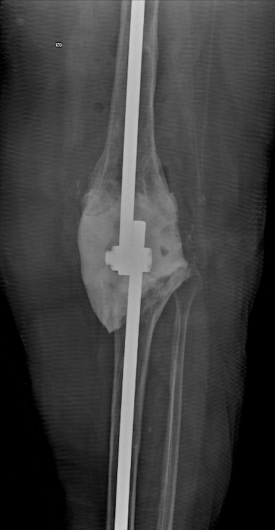

Practico una ortopedia centrada en usted como paciente, moderna, mínimamente invasiva y basada en evidencia científica. Me mantengo en constante actualización nacional e internacional y estoy certificado en cirugía de reemplazo articular con asistencia robótica con el sistema Mako® de Stryker, una tecnología de última generación para el reemplazo de cadera y rodilla, la más avanzada de Latinoamérica y el mundo.

Gracias a la planificación quirúrgica en modelos tridimensionales personalizados, este sistema permite una precisión milimétrica, lo que se traduce en:

Además de la cirugía de reemplazo articular, me especializo en procedimientos de preservación articular y artroscopia de cadera y rodilla, buscando siempre retrasar o evitar la cirugía de reemplazo articular cuando es posible.